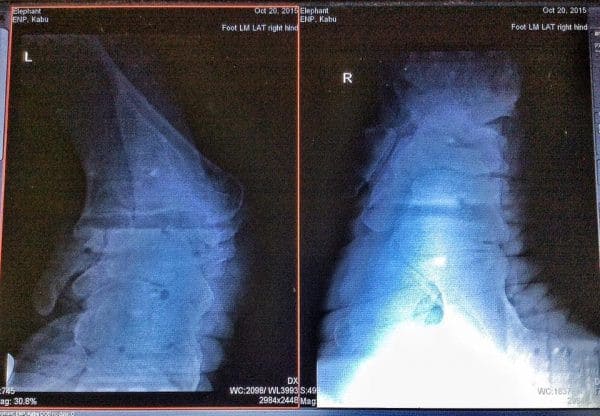

Physically, therapeutic measures aim to restore his body’s natural state through specialized nutrition, medical care, and gentle exercise.